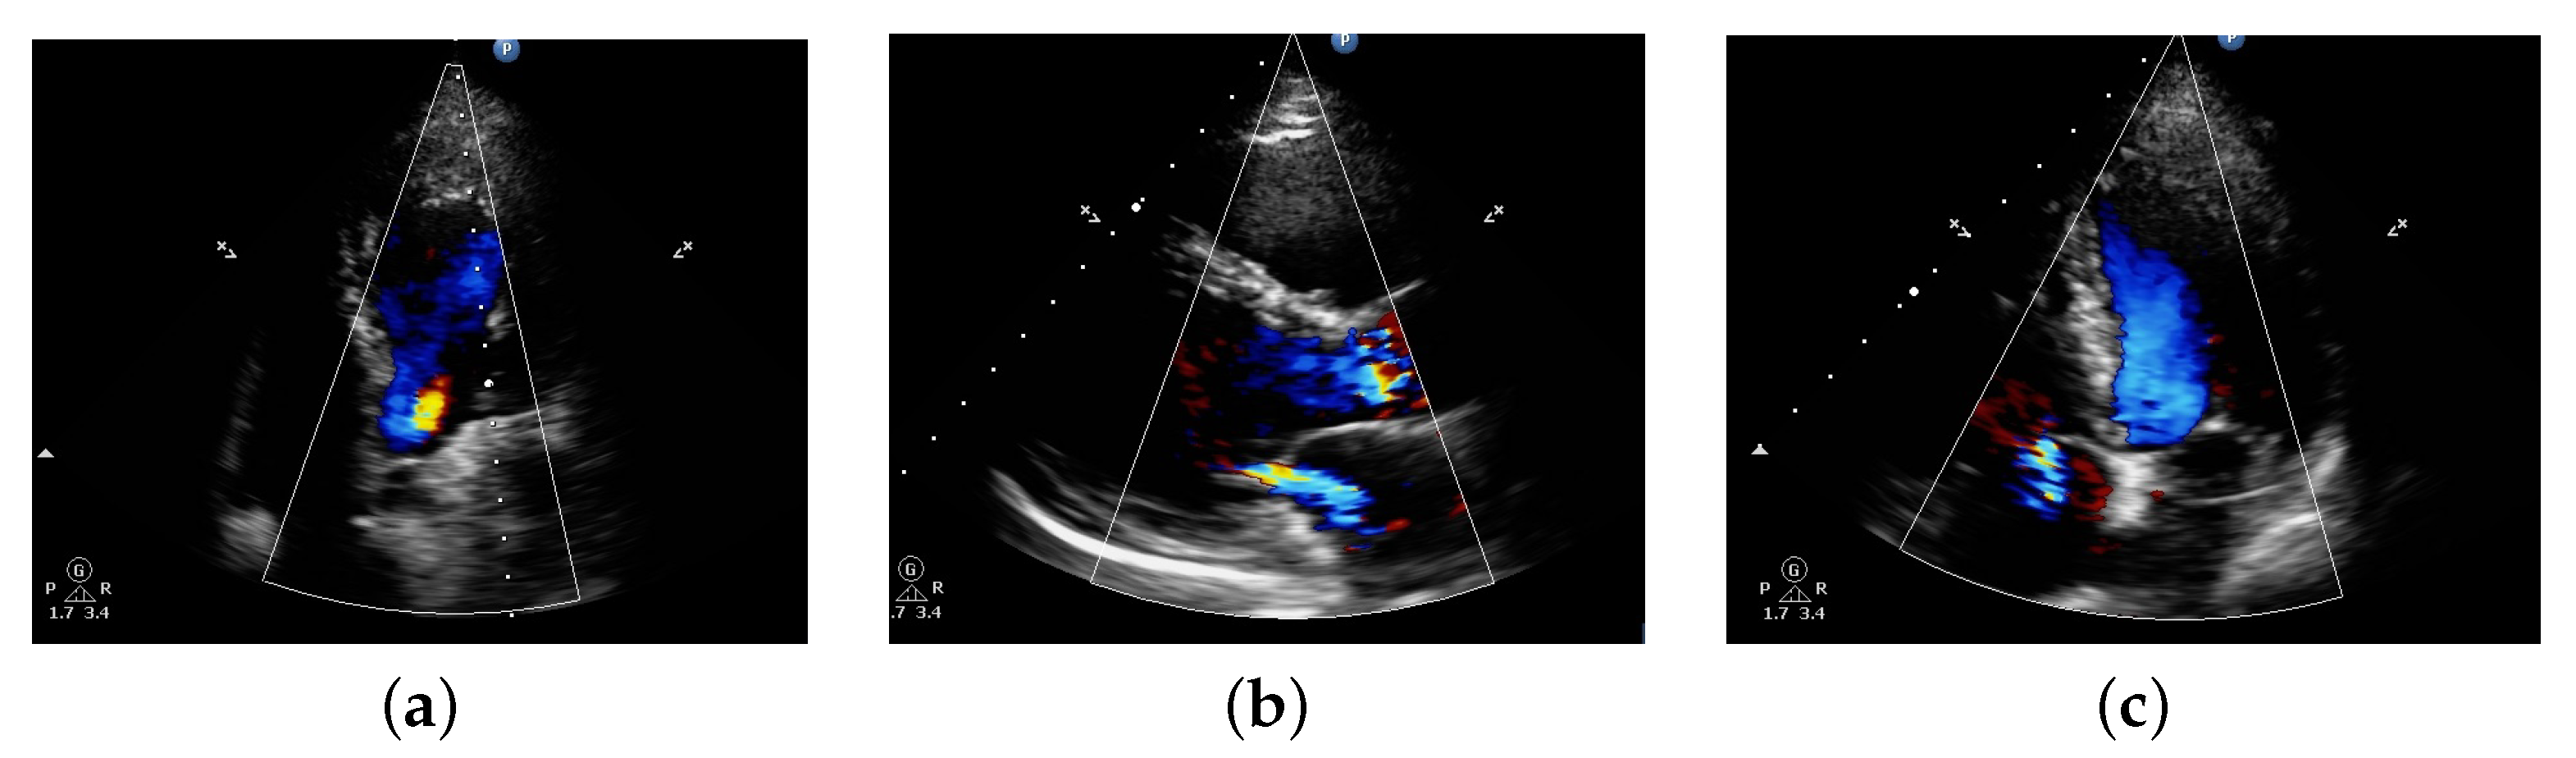

The above mentioned three types of regurgitation are acquired heart disease (cause during one’s lifetime). Not all kinds of regurgitation are known to be acquired, as some can be congenital (presence since birth). In our case, it was observed that all cases of patient data are acquired. Figure 1 shows a Doppler echo having AR, MR, and TR abnormalities respectively. This valvular regurgitation plays a significant role and represents an important cause in mortality and morbidity [9]. The echo plays an essential role in regurgitation assessment and using Doppler echo the presence of the types of regurgitation can be distinguished more distinctively. But this has to be done by a cardiologist by precisely locating and assessing the visualization in the form of video. To detect the presence or absence of any abnormalities, extraction of an image or images from a videographic echo is a necessity. From the visualization of echo, a cardiologist can predict the functions of valves and defective parts, if any. However, It requires trained cardiologists to interpret accurate findings and give reports. Often cardiologists take the help of cauterization [12], which is a surgically invasive and expensive procedure. Usage of automated methods will help in the accurate diagnosis of any heart abnormalities and also reduce the necessity of invasive procedures. There are no automated facilities that can detect the presence of abnormalities or any disease in the heart. Thus, finding a way to treat such abnormalities using automated algorithms is needed. An attempt using machine learning algorithms have been made in the past in which SVM has provided better result using static images. But using videographic images was never explored. For this purpose, work using videography has been introduced to reduce the work of a cardiologist and provide an efficient and effective result as this will help in the early detection and diagnosis of heart diseases.

Figure 1.

Diagram showing Doppler echo from dataset collected of patient having (a) Aortic Regurgitation (AR), (b) Mitral Regurgitation (MR), and (c) Tricuspid Regurgitation (TR) abnormalities respectively.

The raw data were obtained from a Cardiac Clinic namely Hope Clinic loacated in Shillong, India using echo as a tool under the supervison of specialist in the relevant field. A sample image used in the work is shown in Figure 1. The data obtained are in 2D jpeg images, 3D bitmap images, colored and 2D videographic images in Audio Video Interleave (AVI) format. A total of 120 patient data with abnormality/abnormalities cases and a few normal cases were collected. The different types of abnormalities are MR, AR, TR, and a few having mixture of these. All the data are validated with the help of a cardiologist.